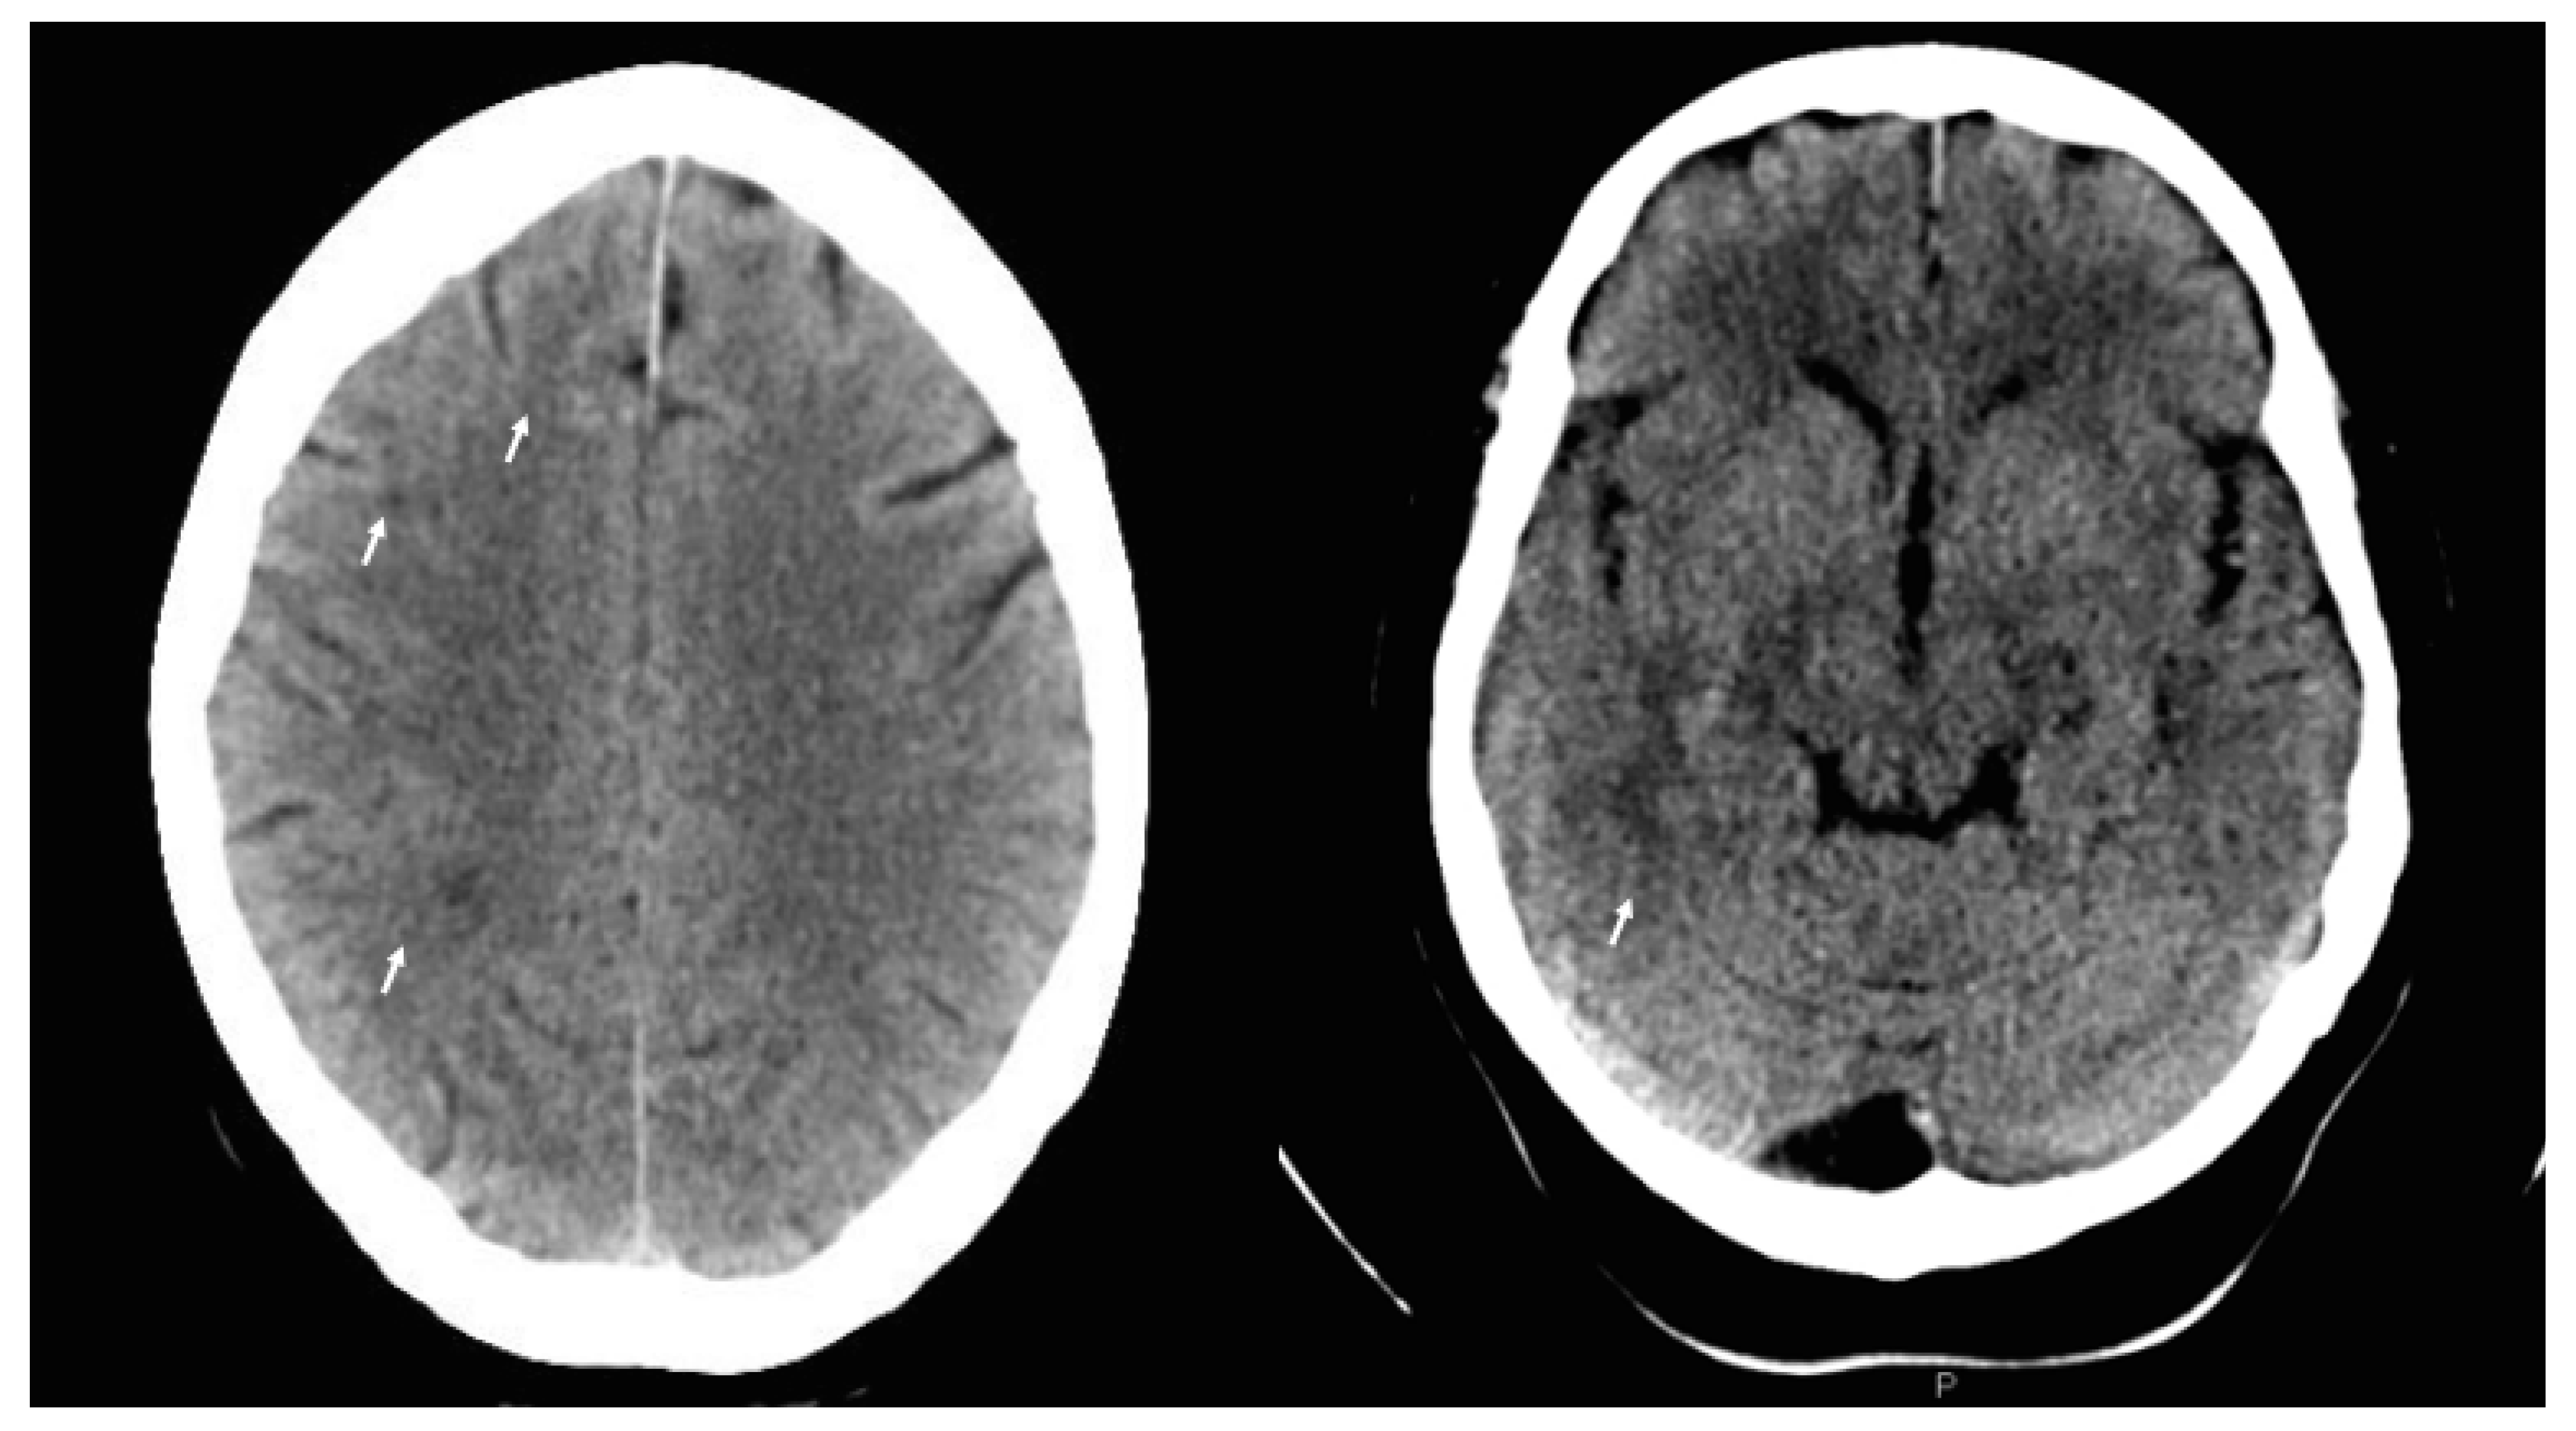

Non-Simultaneous Bilateral Ischemic Optic Neuropathy Related to High Altitude and Airplane Flight in a Patient with Cerebral Small Vessel Disease

2. Case Report